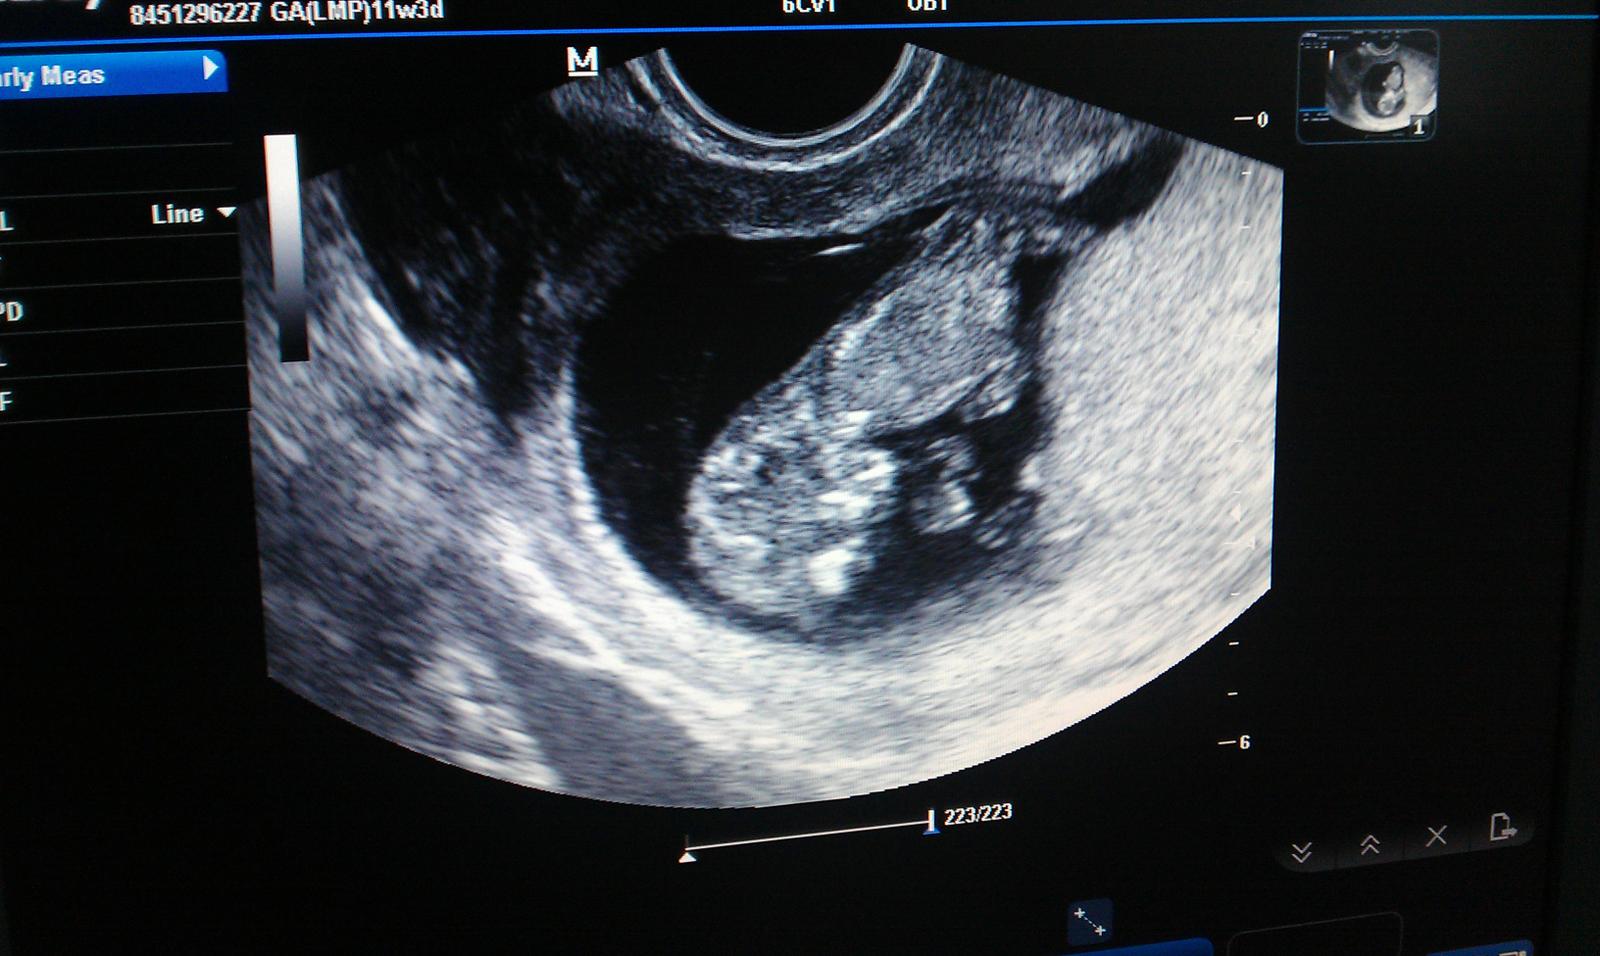

krasna fotecka 😉 Pekne rastiete...len tak dalej 🙂 Sa tesim,ze nas informujes.